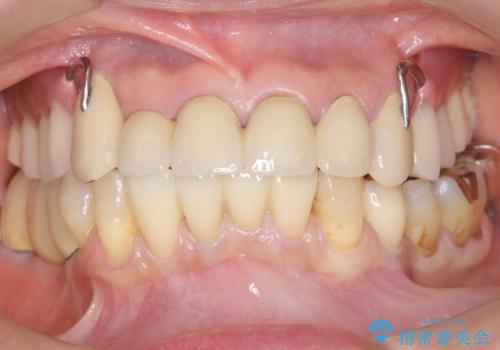

しっかりと咬むことができるようになり喜んで頂けました。

全体的な歯の動揺もなくなり安心して頂けました。

4年経過しましたが問題なく調子が良いとおっしゃって下さいました。

左下のインプラント治療もご希望され、現在治療中です。

被せ物の種類:メタルボンドクラウン エコノミー

インプラントの種類:スプラインツイスト